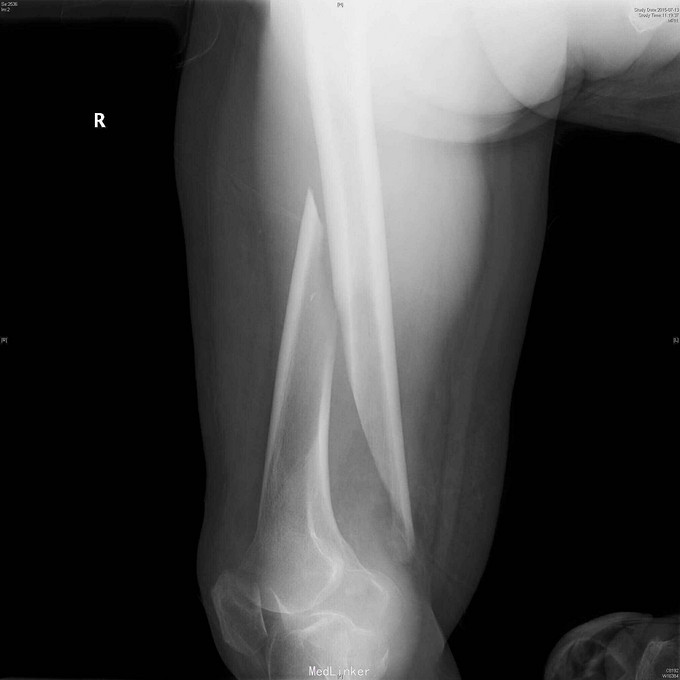

83岁女性,摔倒跪地致右大腿肿胀,疼痛,短缩内翻畸形一天。

查体:右大腿中下段肿胀明显,淤血,压痛,短缩畸形。小腿感觉正常,足背动脉搏动好。 右股骨正侧位片:右股骨中下段长螺旋形骨折,移位短缩明显。